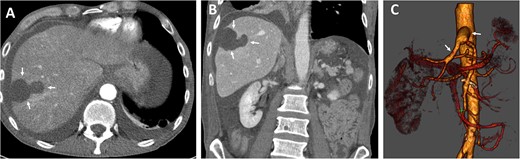

The postoperative recovery was uneventful. We achieved adequate pain control with patient-controlled intravenous analgesia. Inflammation and transaminases levels decreased, and symptoms significantly improved. Diuresis was adequate with normal renal parameters. We performed Partial Thromboplastin Time (PTT)-controlled anticoagulation with a target PTT of 50–60 seconds using intravenous heparin. The patient was transferred to the normal departure on the third postoperative day. Postoperative CT angiography demonstrate enhancement during contrast-enhanced phase and hepatic ischemic area with irregular margins (Fig. 3).

Postoperative axial (A) and coronal (B) CT angiographic images demonstrate enhancement during contrast-enhanced phase and hepatic ischemic area with irregular margins. (C) 3D reconstructed CT angiography shows antegrade visceral reconstruction with a bifurcated graft from the supra-celiac aortic donor to the superior mesenteric and celiac arteries (arrows).